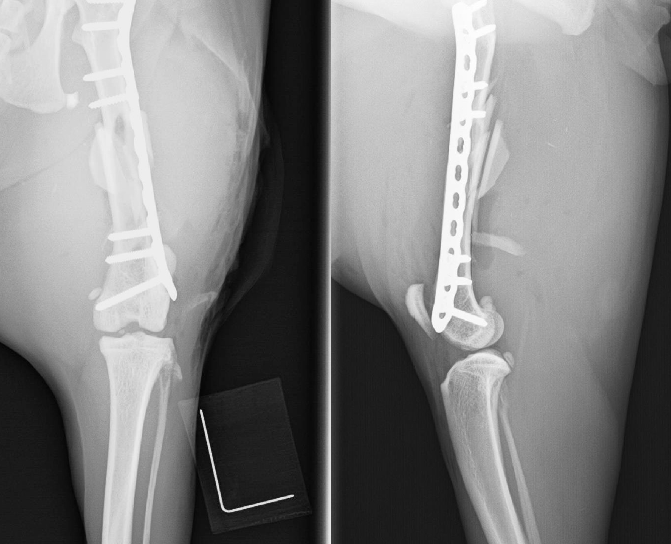

後肢の骨折(骨盤、大腿骨、脛骨)は高エネルギー外傷(交通事故、高い所からの落下など)で全身にダメージを受けている場合があります。

必ず全身状態の評価を行ったうえで整復固定手術を行います。

【術前】大腿骨粉砕骨折プレート整復固定 -

【術後】大腿骨粉砕骨折プレート整復固定 -